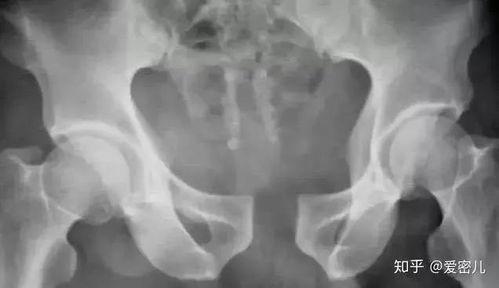

产后骨缝闭合,听起来是不是有点陌生?其实,它是指产后由于骨盆关节松弛,导致骨缝出现一定程度的张开。这种现象在医学上称为“骨盆松弛”。产后妈妈们可能会感到腰酸背痛、下体不适,甚至影响到日常生活。那么,如何判断自己是否出现了骨缝张开呢?